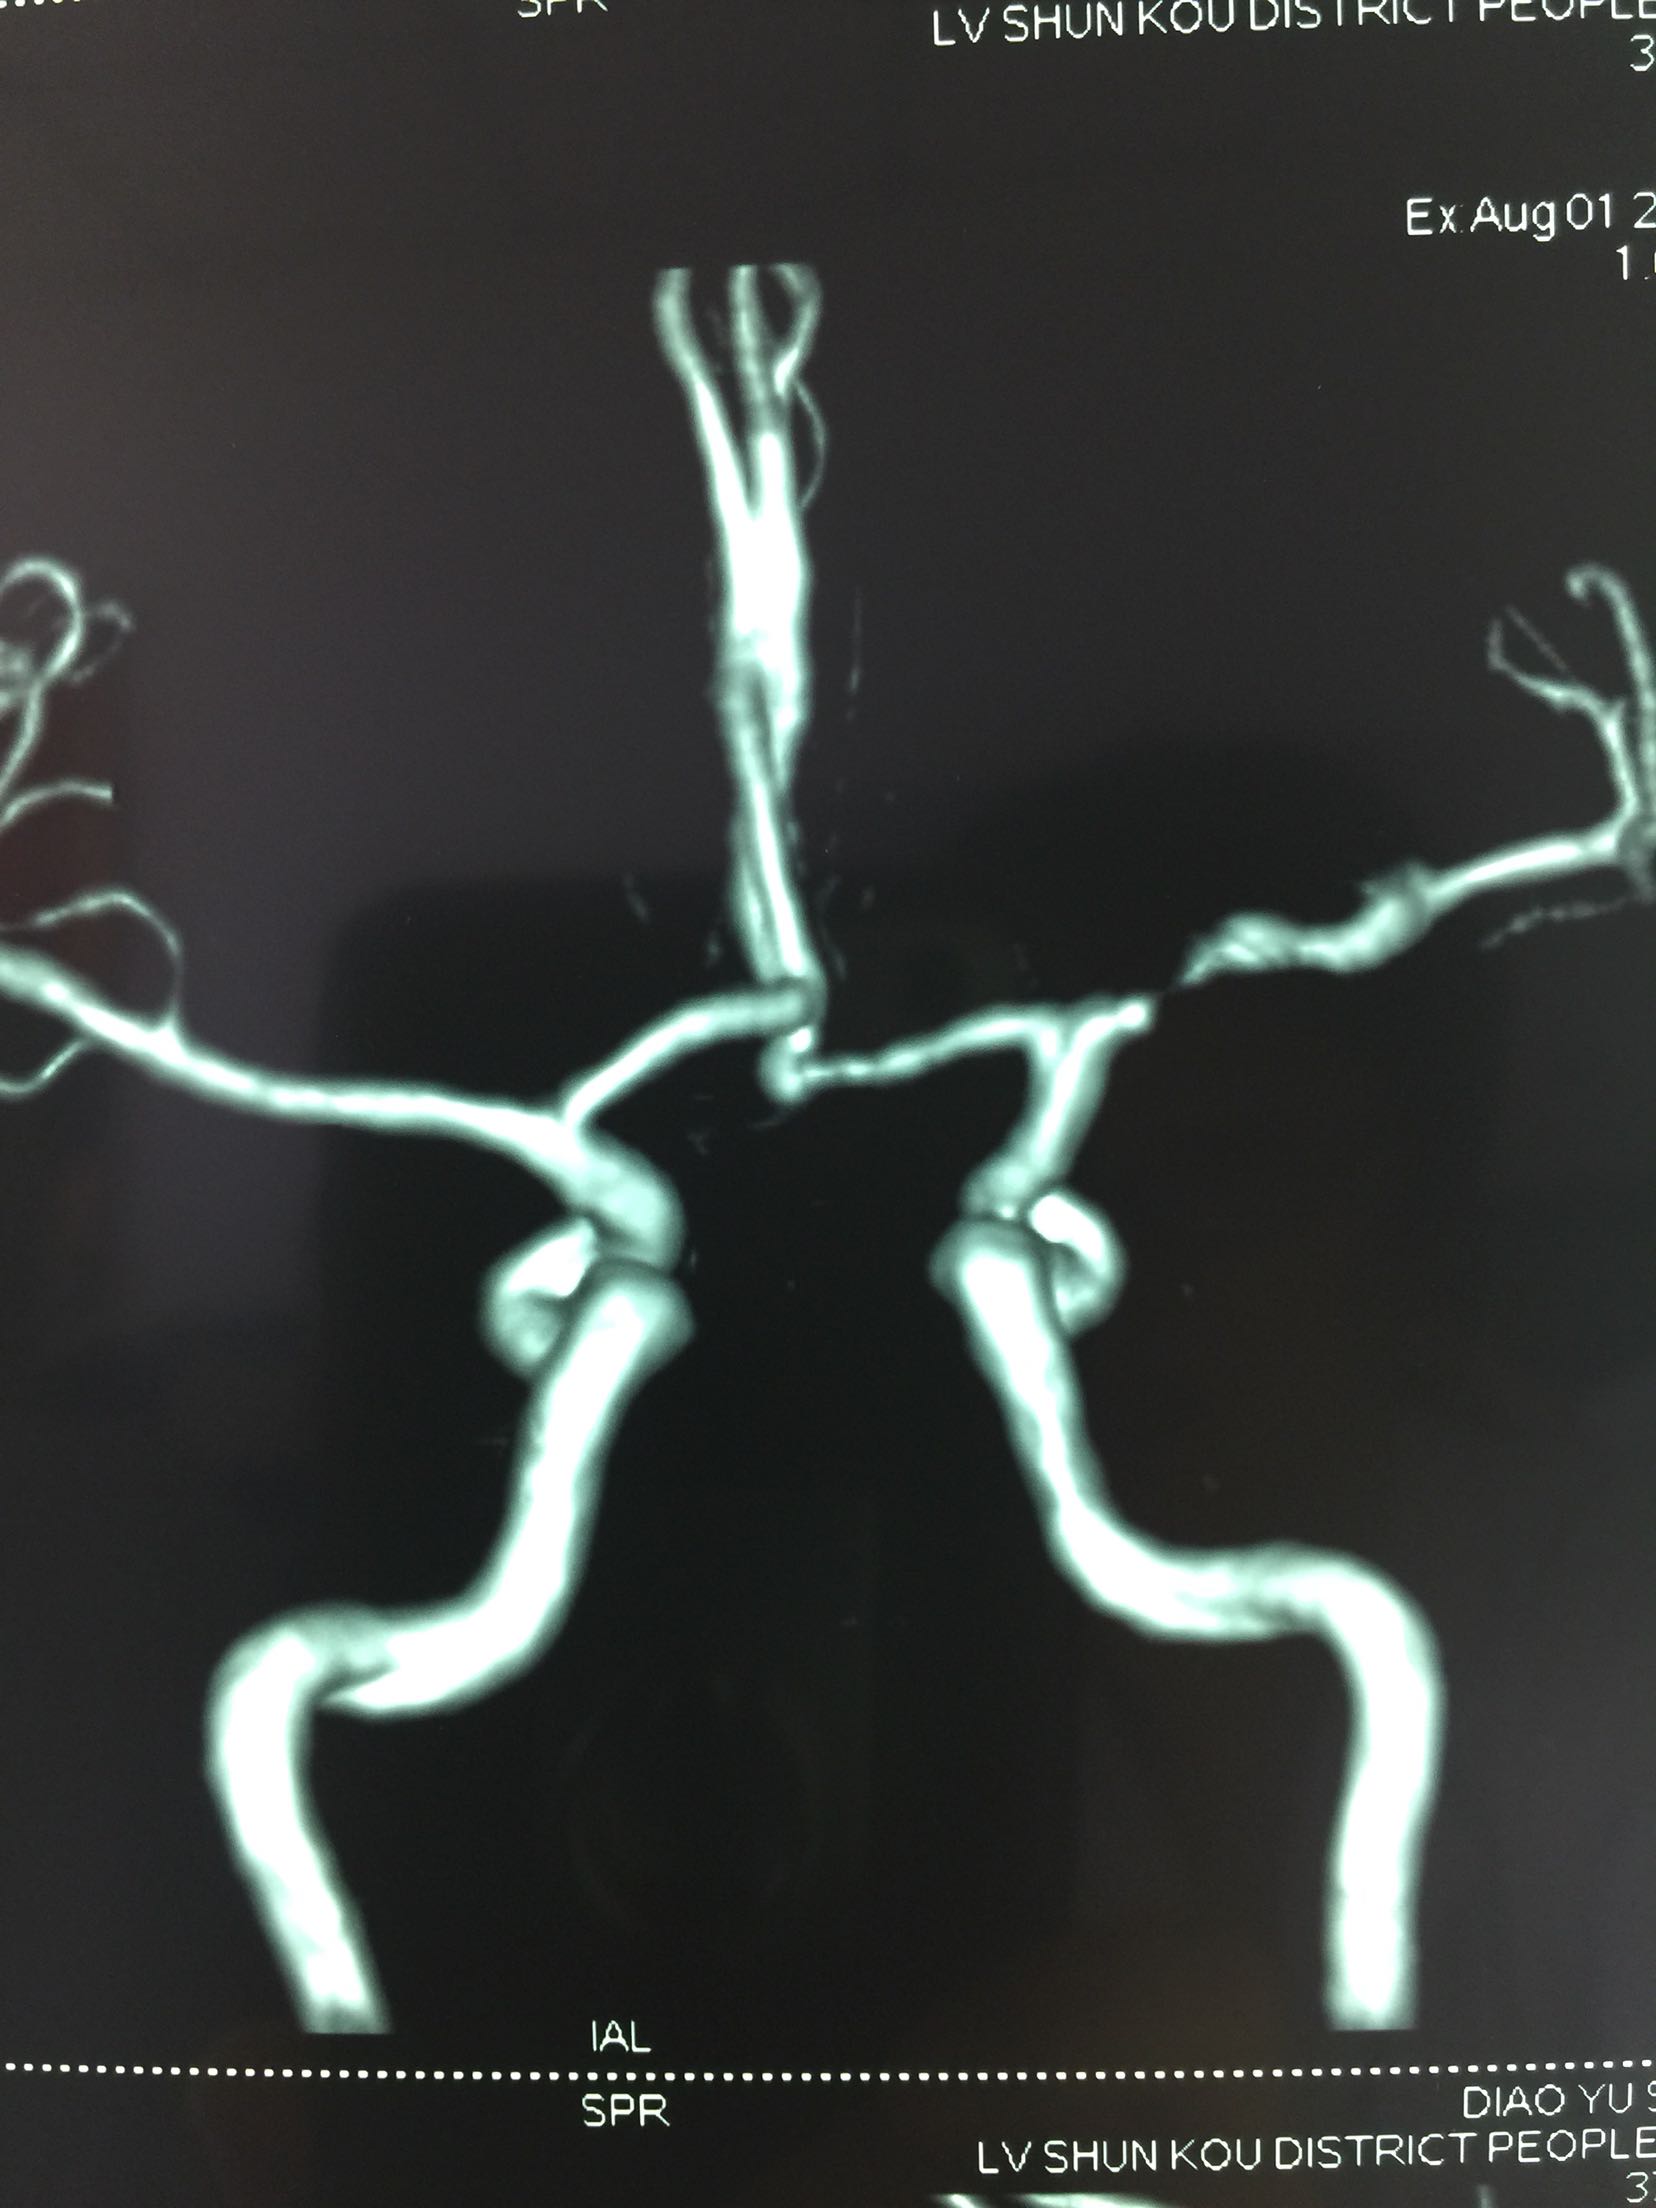

脑梗死 左侧大脑中动脉M1段狭窄

查体:T:36.5℃ P:68次/分 R:18次/分 Bp:120/70mmHg 内科系统:正常 神经系统:神志清楚,言语欠流利,查体合作,平车推人病房。左侧鼻唇沟浅,伸舌左偏,左侧肢体肌力0级,左侧肢体腱反射消失,左巴士征阳性。 辅助检查:血尿常规:正常 肝功、生化:正常 LDL-ch:5.12mmoL/l 心电图:窦性心律 头MRI+MRA、头CTA:

见下图

诊断:脑梗死 右侧大脑中动脉M1段重度狭窄 治疗:阿替普酶溶栓 醒脑静营养神经 长春西汀改善循环 丁苯肽建立侧枝循环 24小时后阿司匹林 氯比格雷抗血小板 瑞舒伐他汀降脂稳定斑块